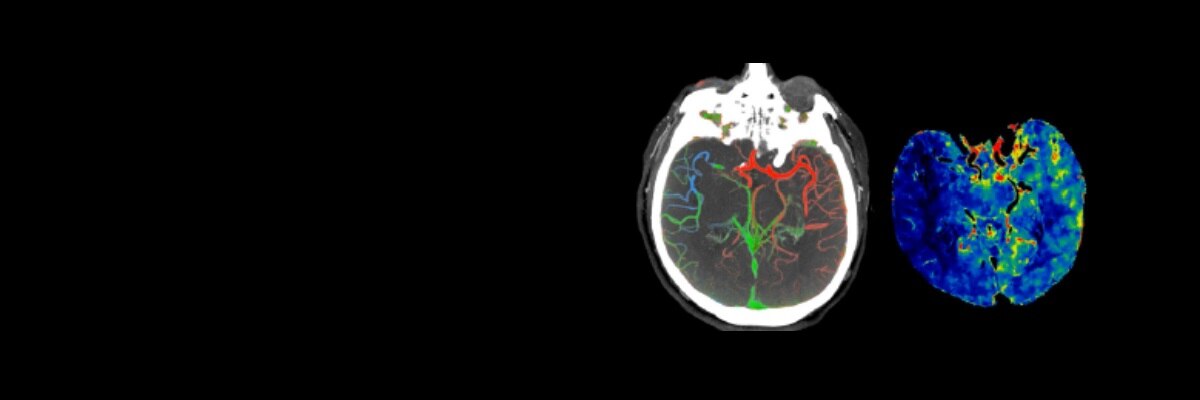

Precision Health in care pathways enable the right outcome, for the right patient,

delivered at precisely the right point of care, using solutions that help improve outcomes, efficiency and cost.

Diagnosis

Planning